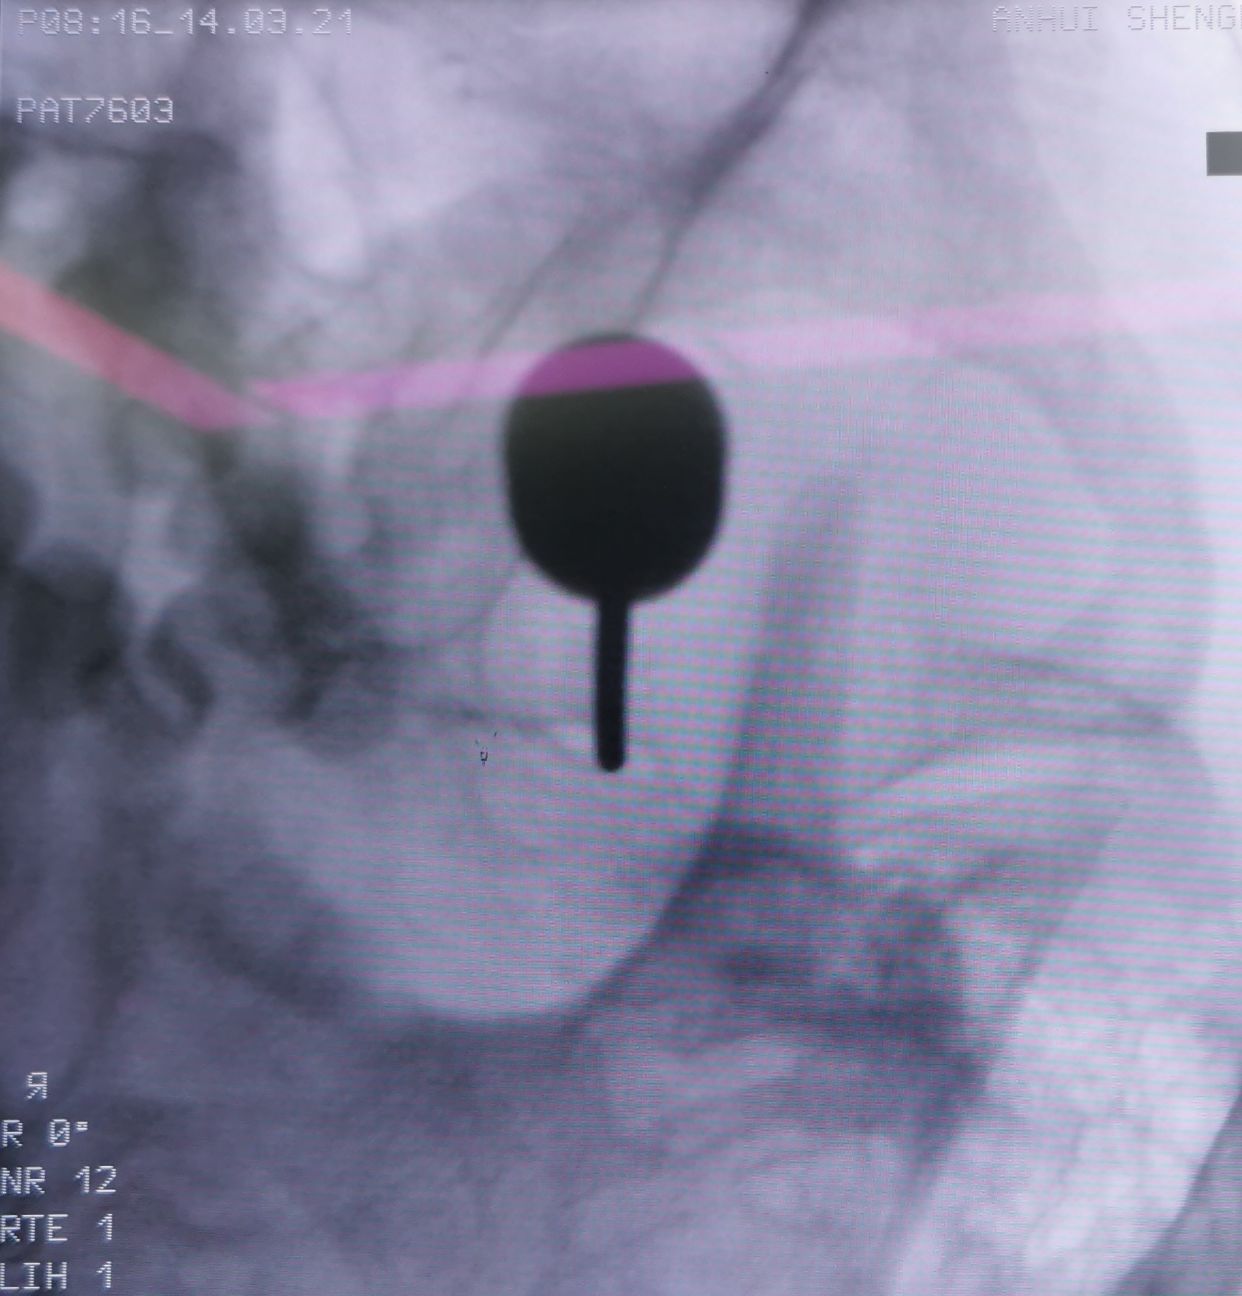

女性,66岁,左侧三叉神经痛

基础疾病多,无法MVD手术,选择PBC

左侧卵圆孔内侧狭小

穿刺针到此,无法进入,骨质完全遮挡

改为中入路

成功